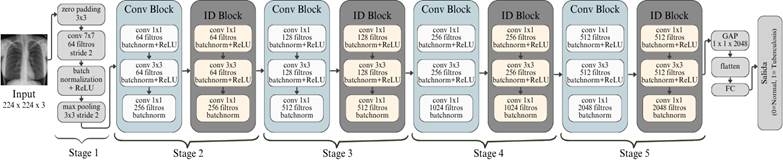

· ResNet50

Figura 5. Arquitectura de ResNet50.

Elaboración: Los autores.

La Figura 5 presenta la arquitectura de ResNet50, una red profunda que se caracteriza por el uso de conexiones residuales que capturan características jerárquicas de las imágenes médicas.

Gracias a esta estructura, ResNet50 es capaz de extraer características altamente discriminativas, logrando un desempeño notable en el diagnóstico de enfermedades pulmonares, incluida la tuberculosis, lo que ha sido validado en estudios recientes que destacan su precisión y robustez en aplicaciones clínicas (Brun et y al., 2021).